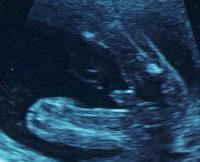

Слышала о таком. Но нам на 17 неделях сказали, что мальчик. И показали со стороны попки... Увидели похожую картинку (фото с инета): image Как видишь, на сроке 17 недель уже мальчика с девочкой перепутать, на мой взгляд, невозможно :))) Разве что аппарат какой-нибудь ужасный... Мы делали в нормальной клинике платно.

если вы думаете что нижняй гигантская штука это писюн-то нет))) это нога))) а выше и правее более размытая- вторая нога))) а вот между ними маленькая штучка это оно))) нам такое на  узи показывали, даже фото тоже есть)))